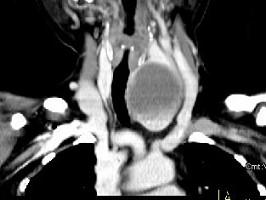

问题 女,56岁 ,发现颈部肿块一月余,CT如图所示,最可能诊断为 ( )

选项 A、甲状腺腺瘤 B、甲状腺脓肿 C、甲状腺乳头状癌 D、甲状腺原发淋巴瘤 E、甲状舌管囊肿

答案 A